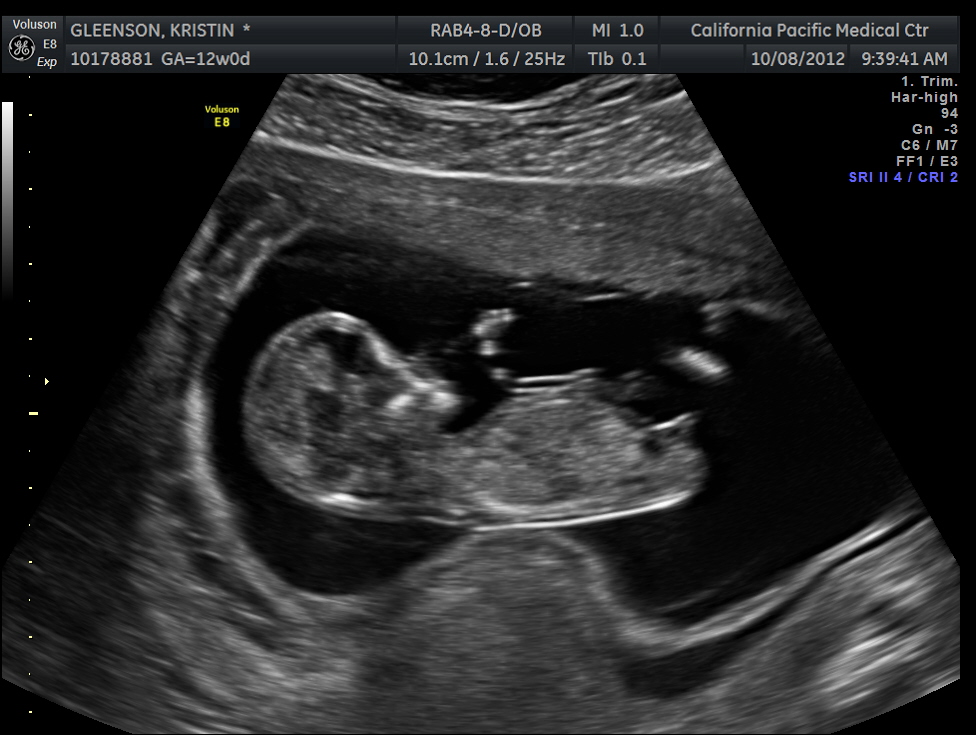

12 week US boy or girl????